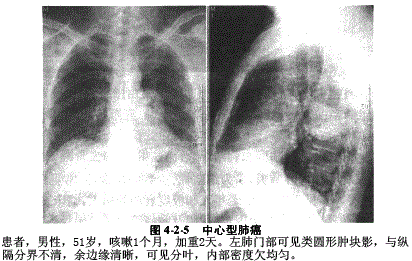

1.中心型肺癌:中心型肺癌是指肿瘤发生于肺段或肺段以上支气管的肺癌,主要为鳞状上皮癌、小细胞癌、大细胞癌及类癌,部分为腺癌。中心型肺癌早期在X线片上可无异常表现,进展期肺癌X线表现有:①肿瘤瘤体征象:显示为肺门肿块阴影,突向肺野,边缘清晰,可见分叶。②支气管阻塞征象:支气管管腔可见不规则狭窄或出现截断现象,支气管管腔不完全狭窄可出现阻塞性肺气肿及阻塞性肺炎,阻塞性肺气肿表现为肺叶体积增大,透亮度增高,阻塞性肺炎表现为局限性斑片状阴影或肺段、肺叶实变影,特点是不易吸收或吸收后短期复发。支气管完全阻塞时发生肺不张,可发生于肺段、肺叶或一侧肺,其体积变小,密度增高,周围结构向病变移位,包括肺门、纵隔、膈及叶间裂移位,右肺上叶不张,下缘与肺门肿块影形成反"S"状,称为反"S"或横"S"征(图4-2-5)。